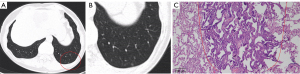

According to pathological results, 93 cases of MPMNs appeared as solitary nodules in 45 cases and multiple nodules in 48 cases. The size of the nodules ranged from 1.0 to 5.0 mm. Nodules manifested with a round shape and well-demarcated borders (100%). We observed nodules close to pulmonary blood vessels.

At low magnification, lung biopsy revealed that the alveolar wall thickened to form multiple small, clear, meningeal epithelioid nodules. At high magnification, the lesions appeared as round, oval, or spindle-shaped cell nests in the lung interstitium with clear cell membranes. Lesions had rich cytoplasm, weak eosinophilia, and fine granular chromatin. Nuclei were elliptical without obvious nuclear atypia, and some cells had very small nucleoli without obvious mitotic patterns. After reviewing the original data and supplementary tests, 13 cases had IHC results, but the rest of the lesional cells were small and disappeared after immunolabeling sections. The lesional cells showed consistent positive expression of vimentin (100%), followed by epithelial cell membrane antigen (92.3%) and PR (8%).

Comparison of the size, shape, edge, opacity, and vascular relationship of individual details from CT imaging results showed good concordance with the pathology results. Therefore, pathology results could explain the appearance of different features observed by CT imaging.

Nodule size on CT scans ranged from 2.5 to 5.0 mm, with an average size of 3.04±1.12 mm. Nodule size ranged from 1 to 5 mm under the microscope. The nodule size measured on CT was larger than the corresponding pathological measurement. The MPMNs appeared as round nodules on images and oval nodules under the microscope. As the alveolar space was still inflated, nodules were inevitably squeezed during surgery, resulting in the small difference in measurement results.

Lung nodules in 46 patients were all well-defined. We could observe multiple nodules in one field of sight and outline them through a low-power microscope. They appeared with clear boundaries on images. Through imaging and comparison by pathology, it can be inferred that the disease originates from the lung interstitium.

Most MPMNs showed GGO (97.8%). According to pathology observations, lesions originated from the alveolar interstitium rather than alveolar epithelial tissue. The lesions grew along the alveolar septum, leading to interstitial lung hyperplasia. However, the pulmonary alveoli were still inflated, so CT scans showed a GGO. Part of the nodules appeared to have a cyst-like morphology. We speculated that the pathological basis might be that the obvious pulmonary interstitial hyperplasia and contraction lead to abnormal expansion of the adjacent alveolar ducts or bronchiole, leading to a central low-opacity shadow in part of nodules (15).